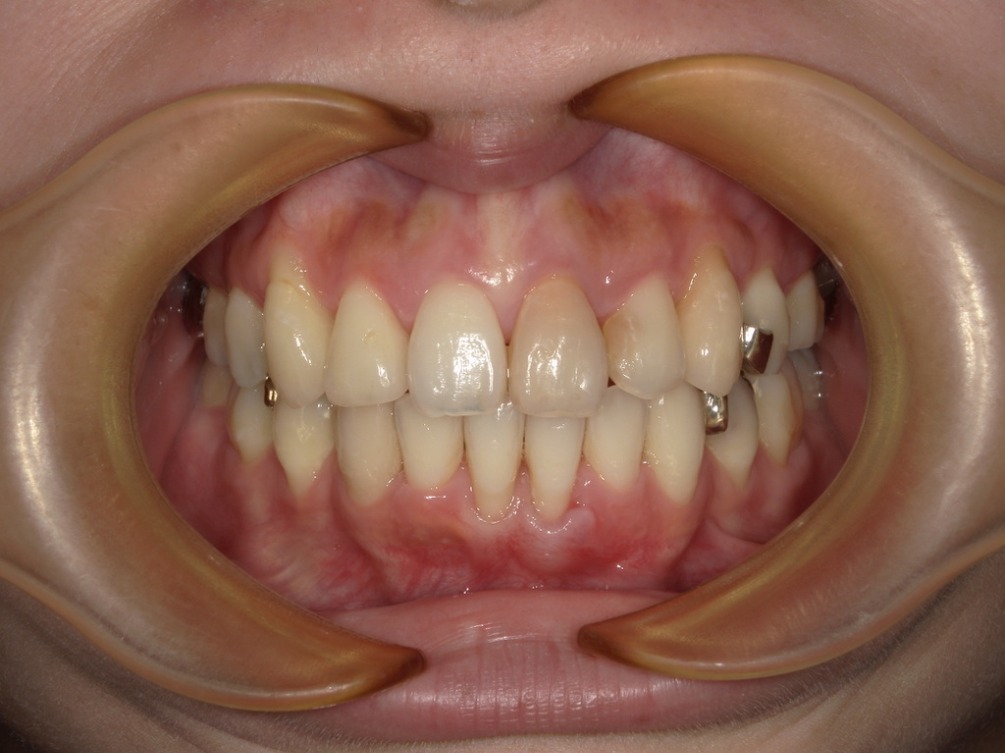

上下の歯の真ん中がずれているのはわかりますか?

「正中」とは、顔の中心を通る縦のラインのこと。

鼻・唇・あごなどの中心を結ぶ線を基準として、

上の前歯の真ん中(上顎正中)と下の前歯の真ん中(下顎正中)がこの線上で揃っている状態が理想的な噛み合わせです。

一方で、

- 上下の歯の中心がずれている

- 歯列全体が顔の中心から左右どちらかにずれている

このような状態を「正中ズレ」と呼びます。